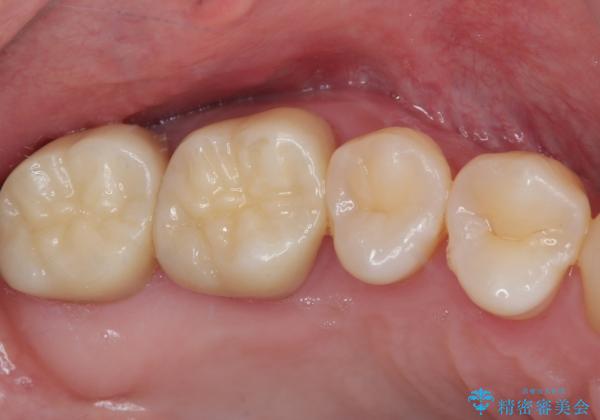

奥歯が痛い オールセラミッククラウンでのむし歯治療

- 他院で矯正治療前後に処置を行った歯が痛むとのことで来院された患者様です。

下顎大臼歯は根管治療がされている歯が咬合時に痛みを感じ、上顎の大臼歯2歯は冷たいものがしみる状態でした。

まずはしみる上顎の歯を仮歯に置き換え、その後下顎の根管治療を行った上で、異常が認められなければオールセラミッククラウンにて補綴治療を行うこととしました。

上顎は仮歯に置き換えた後に、それまでの痛みは一切感じなくなり、下顎も一度目の根管治療で痛みを感じることはなくなりました。